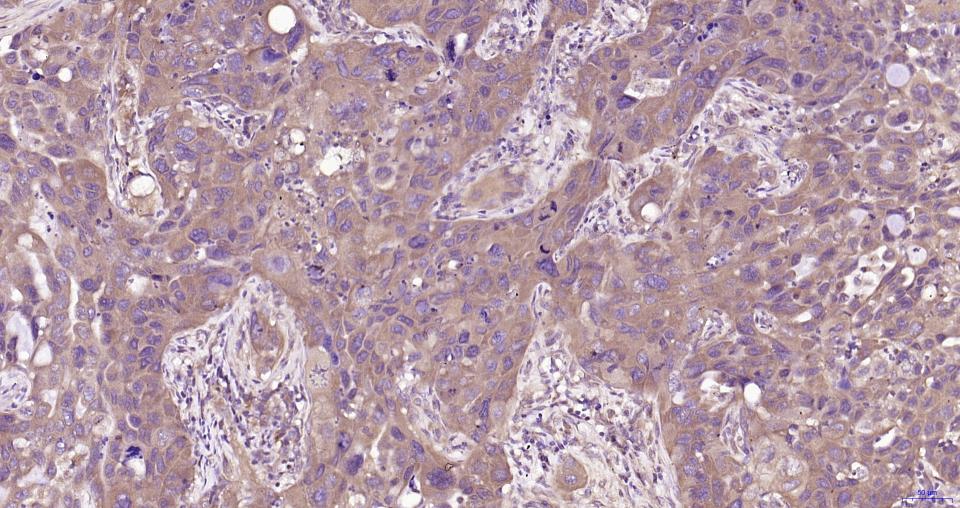

Paraformaldehyde-fixed, paraffin embedded Human Lung Cancer; Antigen retrieval by boiling in sodium citrate buffer (pH6.0) for 15 min; Antibody incubation with MyD88 Monoclonal Antibody, Unconjugated(bsm-61269R) at 1:200 overnight at 4°C, followed by conjugation to the SP Kit(Rabbit, SP-0023) and DAB (C-0010) staining.